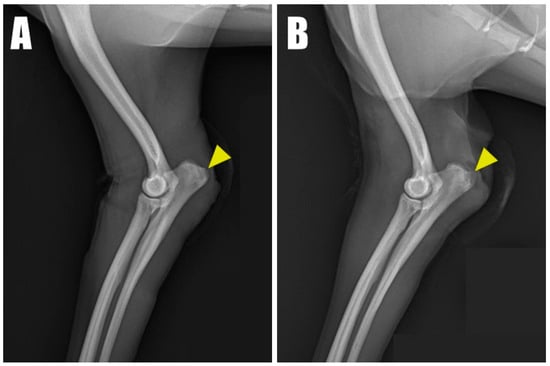

A 2-year-old, 4.5 kg, intact female Pomeranian was referred to a veterinary medicine teaching hospital with bilateral open wounds (Video S1, Figure 1A) at the olecranon region. The dog presented with a history of bilateral forelimb lameness and crouch gait (Figure 1B) as follows: four weeks in the left forelimb and three weeks in the right forelimb, each following a fall from a height. Physical examination revealed a pain response and nodular formation in the proximal region of the olecranon, with no extension response during the triceps brachii squeeze test. Radiographs revealed radiolucent opacities on both sides of the olecranon (Figure 2A,B), and ultrasonography identified defects (Figure 3A,B) at the triceps brachii tendon and olecranon junction, accompanied by inflammation and edema. Notably, the distal end of the proximal tendon appeared hyperechoic compared with the normal tendon. Based on the diagnosis of bilateral triceps brachii tendon disruption, believed to be of traumatic origin, and with the exact cause remaining open to interpretation, surgical repair was indicated. The initial management of the open wounds involved sugar dressing and debridement. Pre-anesthetic evaluation through blood samples, assessing electrolytes, and complete blood count (CBC), revealed all values within normal limits.

Figure 2. Radiolucent opacity (yellow arrowhead) was visible on the olecranon in radiographic images of the (A) right and (B) left forelimbs.